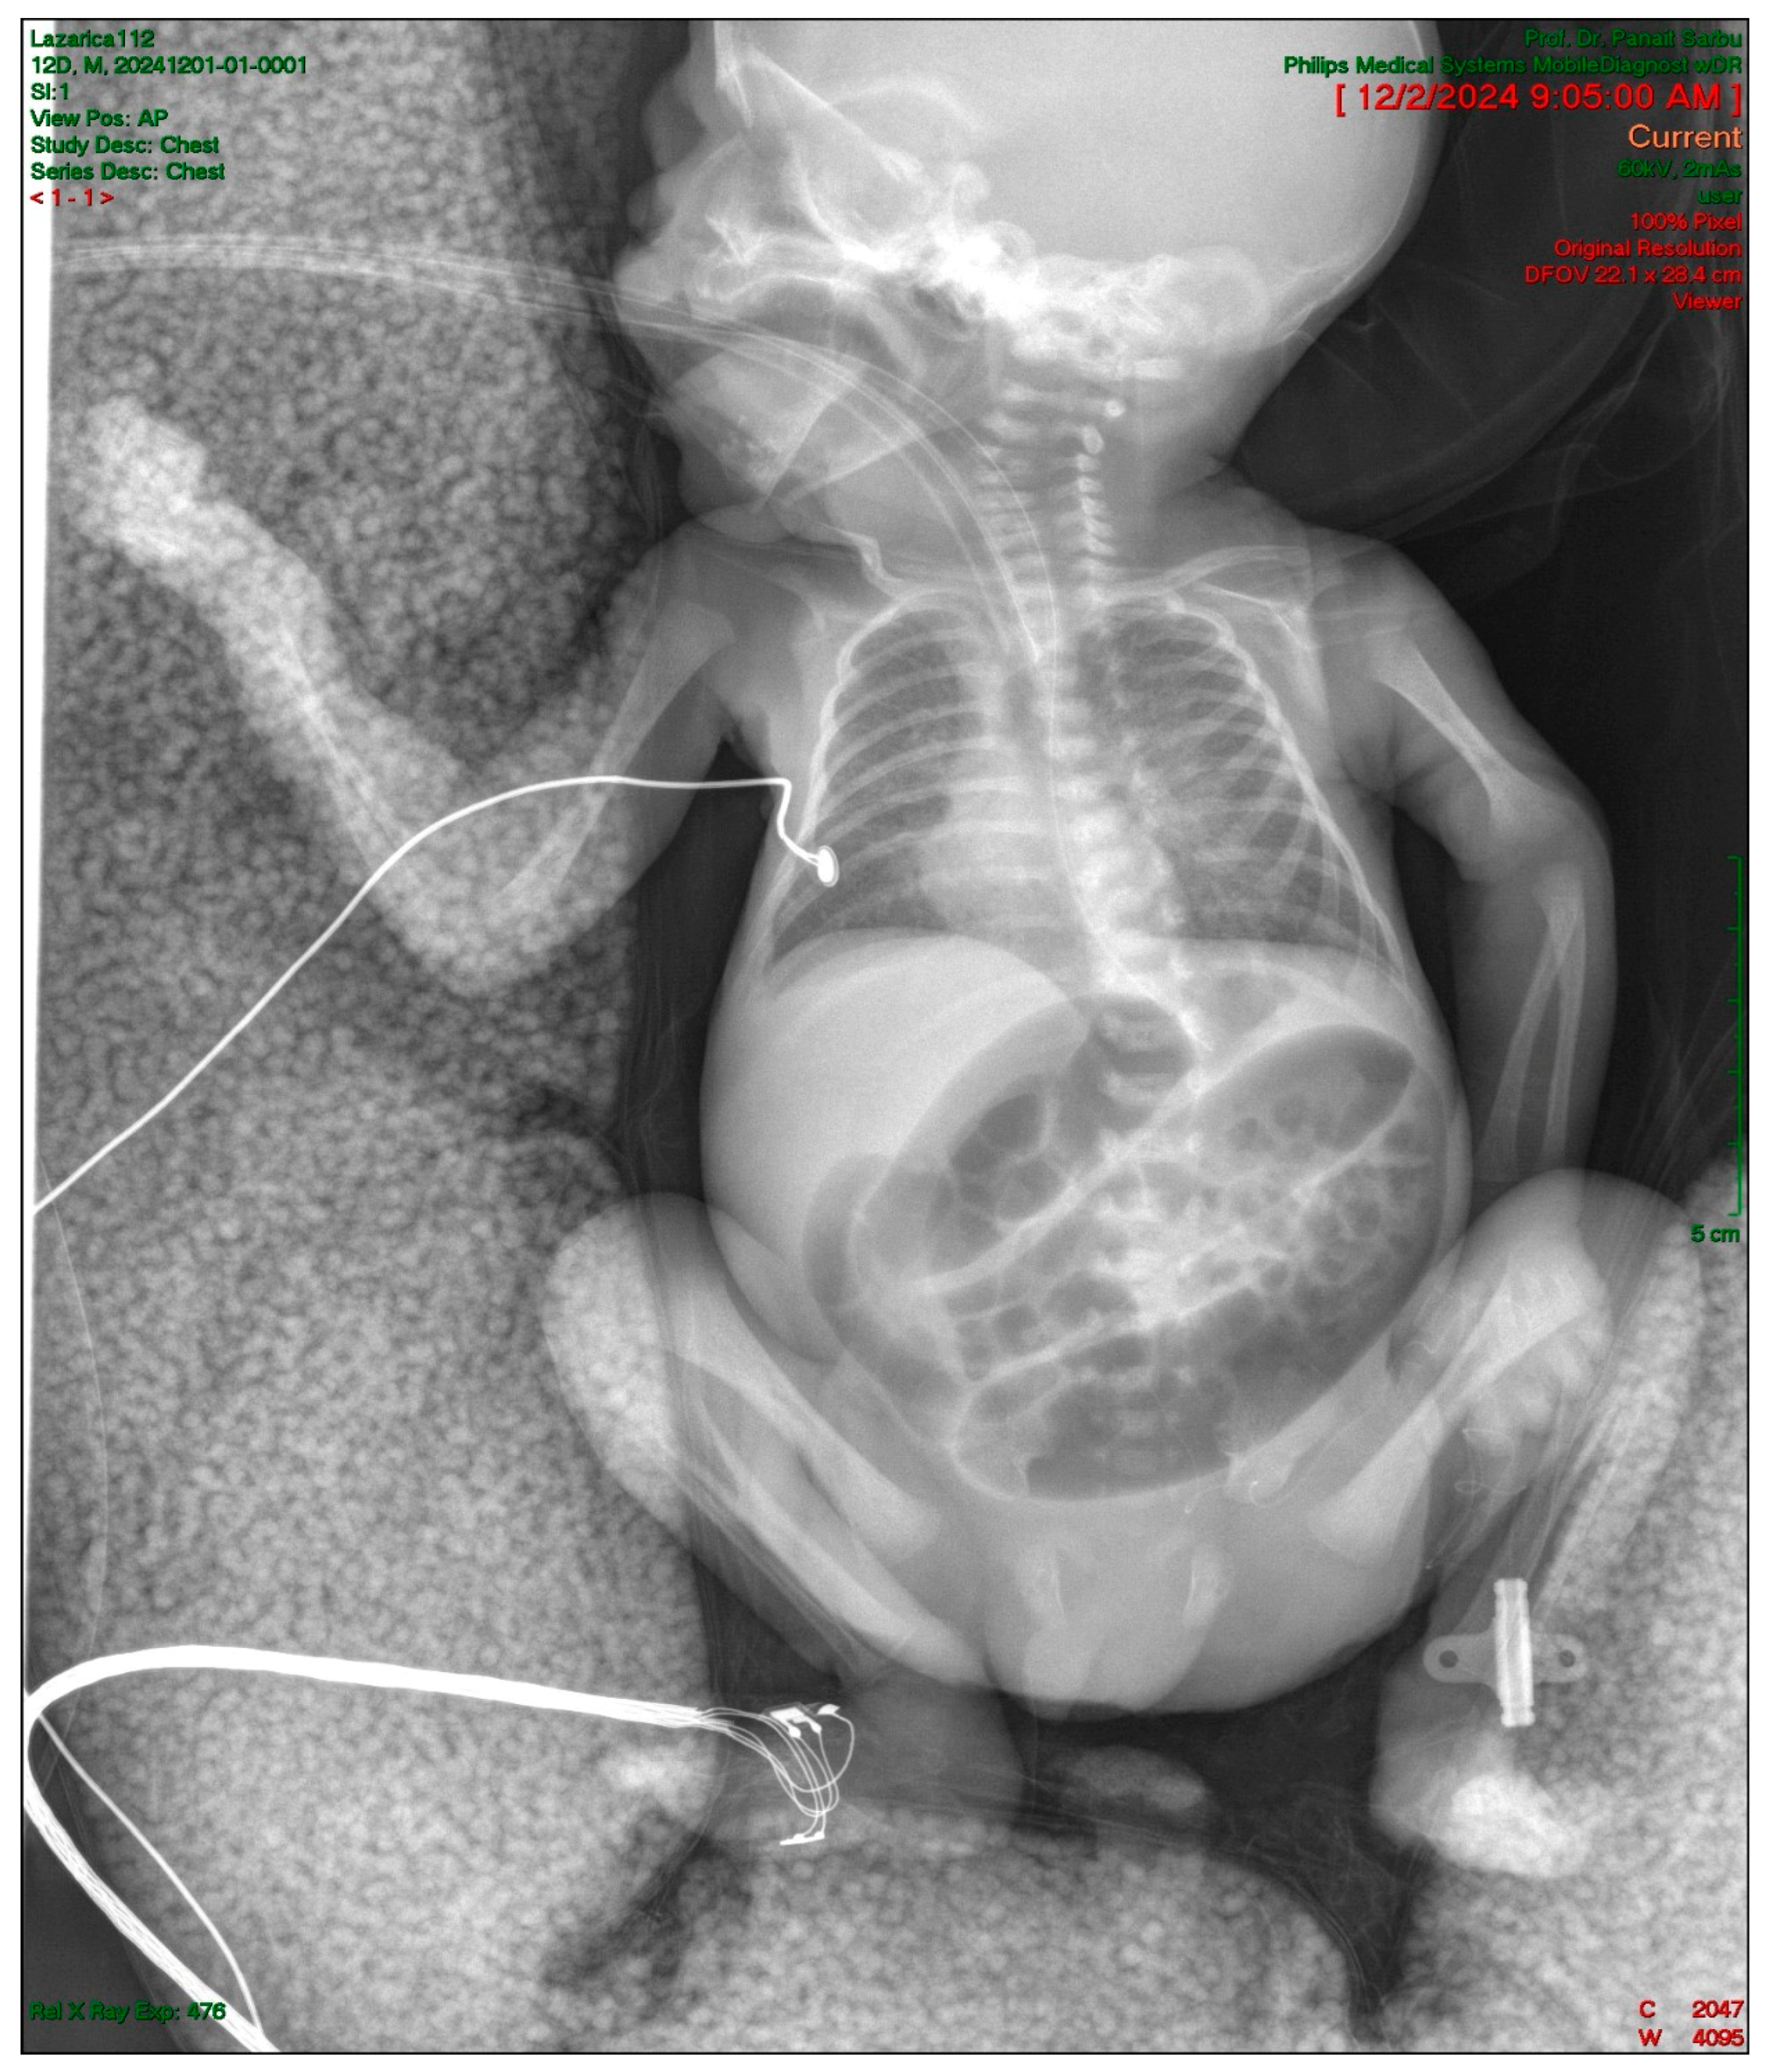

2.4. Gastrointestinal Complications and Diagnosis

2.5. Postoperative Course and Complications

| Day 12 | Intestinal obstruction suspected | Surgical consultation |